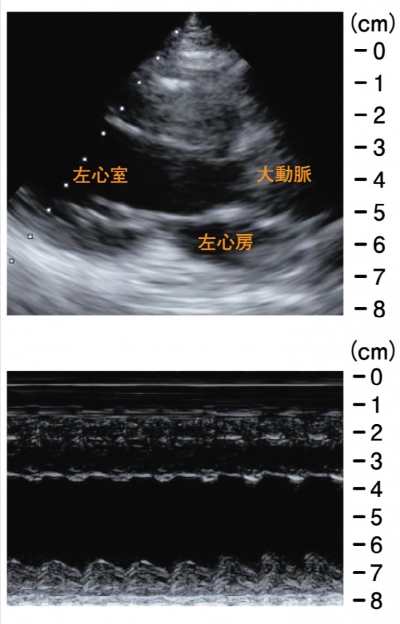

血液所見:赤血球 482 万、Hb 14.1 g/dL、Ht 41 %、白血球 14,200、血小板 17 万。血液生化学所見:総蛋白 6.4 g/dL、アルブミン 3.8 g/dL、総ビリルビン 1.1 mg/dL、AST 519 U/L、ALT 366 U/L、LD 983 U/L(基準 176〜353)、CK 222 U/L (基準 30〜140)、 尿素窒素 23 mg/dL、クレアチニン 1.0 mg/dL、血糖 199 mg/dL、Na 128 mEq/L、 K 4.4 mEq/L、Cl 99 mEq/L。CRP 2.1 mg/dL。心筋トロポニン T 陽性。動脈血ガス分析(room air):pH 7.32、PaCO2 20 Torr、PaO2 55 Torr、HCO3 10 mEq/L。 仰臥位のポータブル胸部エックス線写真、心電図及び心エコー図を示す。